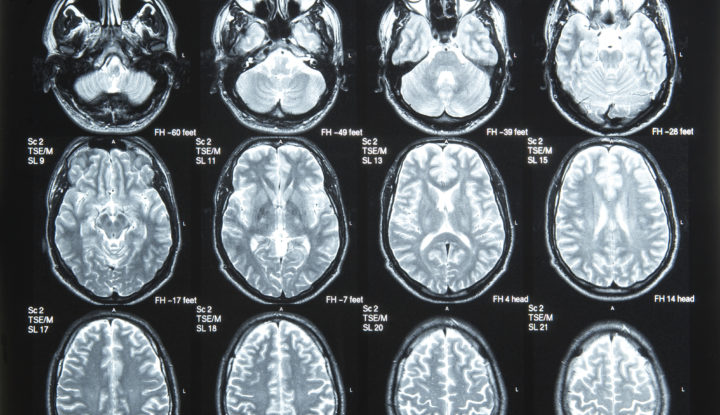

A Rhode Island Kórház orvosainak egy év alatt háromszor sikerült rossz oldalon végezni agyműtétet. Az utolsó eset 2007-ben történt, ekkor az idegsebész a bal helyett a jobb oldalon fúrta meg 82 éves betege koponyáját. Ő szerencsére “időben” észrevette mit csinál, bezárta a sebet majd folytatta a műtétet a megfelelő oldalon.